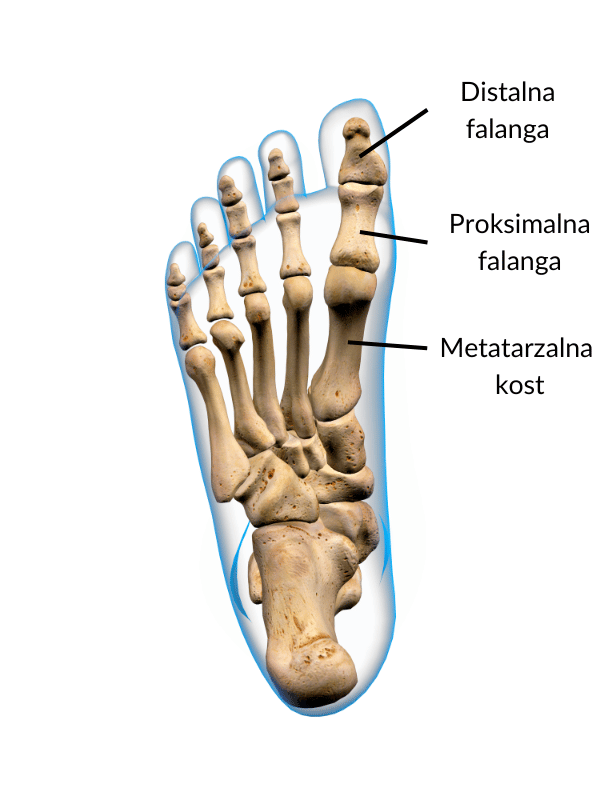

Anatomija stopala

Skoraj četrtina vseh kosti v človeškem telesu se nahaja v stopalih. Stopala so kompleksna in fleksibilna struktura, sestavljana iz številnih kosti, sklepov in več kot 100 mišic, tetiv in vezi. Vse skupaj kot celota omogoča gibanje in ima zelo pomembno vlogo v ravnotežju celotnega telesa.

Nožni palec oz. hallux je sestavljen iz metatarzalne kosti ter iz proksimalne in distalne falange. Gibanje nožnega palca zajema upogib (krčenje palca), izteg (dvig palca) in odmik. Na palec se pripenja kar sedem mišic, ki omogočajo mobilnost in stabilnost palca.

Pri hoji je zelo pomembno, da lahko dosežemo normalen izteg palca, kar se zgodi v fazi odriva. Nepopoln izteg palca negativno vpliva na stabilnost stopalnega loka in plantarno fascijo. V primeru hallux valgusa je gibljivost palca zmanjšana in eden od pomembnejših gibov, ki ga moramo ponovno pridobiti, je ravno izteg.